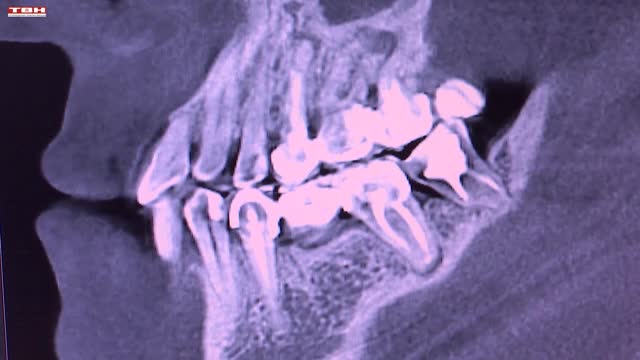

Неделя ответственного отношения к здоровью полости рта – повод вспомнить о визите к стоматологу. Делать это надо раз в полгода, даже если ничего не болит. Профилактические осмотры помогут выявить заболевания крови, эндокринной системы, и конечно, желудочно-кишечного тракта.

Научные исследования установили взаимосвязь между потерей зубов и болезнью Альцгеймера, нездоровая полость рта может привести к мужским болезням. Онкологию тоже можно заподозрить во время приема у дантиста.

Оксана РУСАКОВА, заведующая стоматологическим отделением НГКБ № 29 им. А.А. Луцика: «Люди иногда привыкают к каким-то новообразованиям в полости рта, зачастую они не причиняют ему никаких дискомфортов. Это могут быть и доброкачественные новообразования, которые могут много лет никуда не развиваться, но это еще бывают и факультативы, которые в любой момент могут развиться в патологическую сторону, в сторону онкологии. Мы по изменениям от нормы уже можем дифференцировать визуально и назначать дополнительные диагностические исследования».